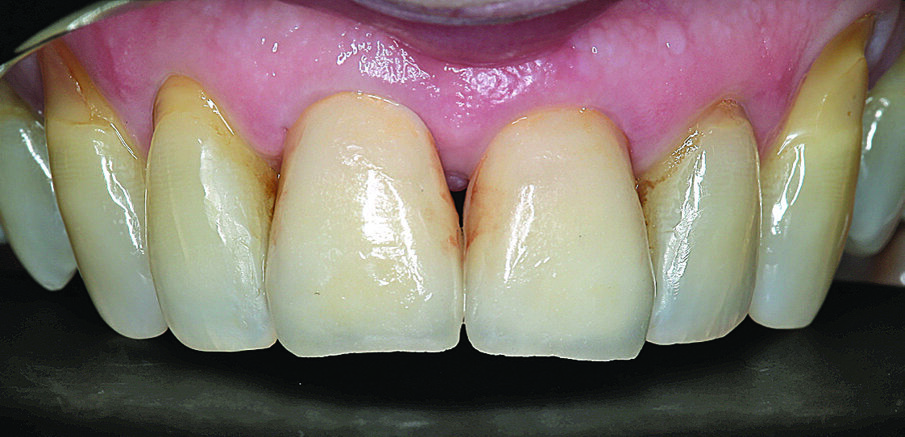

Budući da se to nije moglo isključiti za zub 21, u narednim posjetima provedeno je endodontsko liječenje s naknadnim punjenjem korijenskog kanala s MTA-om do pukotine (Slika 3.). Budući da je pacijent izrazio želju da se ne narušava estetika, za splintiranje je upotrijebljena palatinalna udlaga od PMMA-e (Slika 4.). Nakon tri mjeseca uočena je sve veća promjena boje zuba 21 i perzistentna pomičnost II. stupnja (Slika 5.). Nakon detaljnog informiranja o raznim mogućnostima liječenja kliničar i pacijent donijeli su odluku o implantoprotetskoj terapiji. CBCT snimljen tijekom planiranja terapije (Slika 6.), pokazao je blizak odnos prema vestibularnoj koštanoj lameli (položaj korijena I. razreda)14. Da bi se stvorio stabilan profil mekog i tvrdog tkiva i pacijentu što prije osigurao dobar estetski rezultat, kliničar se odlučio na imedijatnu implantaciju uz primjenu socket shield tehnike.

Slika 1. Početna situacija: Frontalni prikaz reponiranih i splintiranih zubi 11 i 21